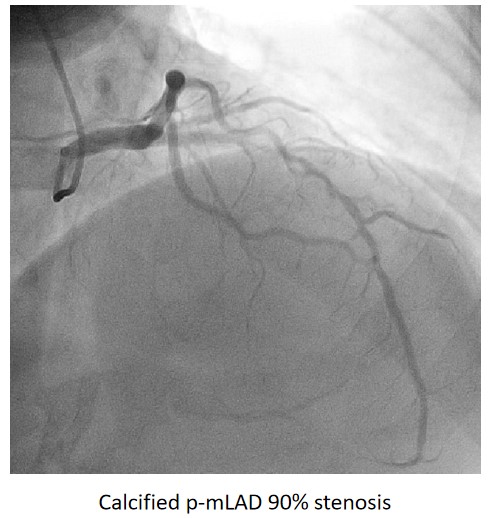

Urgent coronary angiography showed smooth LMCA with severe 3-vessel involvement. There was diffuse LAD lesion with critical stenosis at proximal-to-mid segment. Mid-segment of LCx was 90% stenosed while RCA was heavily calcified with critical stenosis at its mid segment. Our strategy will be complete revascularisation by employing DCB-only strategy.

Complete revascularisation was achieved with 2-staged procedures. Up-front plaque modification with rotational atherectomy/IVL with IVUS was planned but limited by patient¡¯s cost constraint. Vascular access obtained with transradial puncture with 6 Fr sheath. Guiding catheter (GC) Judkins Right 4.0 (Cordis, USA) 6 Fr was used to engage right coronary ostium. Runthrough Floppy (Terumo, Japan) wire was wired down RCA. Pre-dilatation balloons were unable to cross the heavily calcified mRCA lesion. Next, GC was changed to Amplatz Left 1.0 (Cordis, USA) for better support and proceeded for further lesion preparation with cutting balloon Wolverine (Boston Scientific, USA) 3.5 x 10 mm and DCB Prevail (Medtronic, USA) 3.0 x 20 mm was deployed. We scheduled him for staged PCI to the left coronaries in 2 weeks time via transradial approach with 6 Fr sheath. GC XB LAD 3.5 (Cordis, USA) 6 Fr was used to engage left coronary ostium. Runthrough Floppy was wired down LCx. Mid-distal LCx was prepared with Pantera Pro (Biotronik, Germany) 2.5 x 15 mm and DCB Pantera Lux (Biotronik ,Germany) 3.0 x 15 mm was deployed. Finally, we wired down LAD with Runthrough Floppy. Mid-distal LAD lesion was prepared with Pantera Pro 2.5 x 15 mm and DCB Pantera Lux 3.0 x 30 mm was deployed. Proximal LAD lesion, which was calcified, was further prepared with Wolverine 2.5 x 10 mm before DCB Pantera Lux 3.5 x 30 mm was deployed. Final post-PCI results were acceptable, achieving complete revascularisation for him.